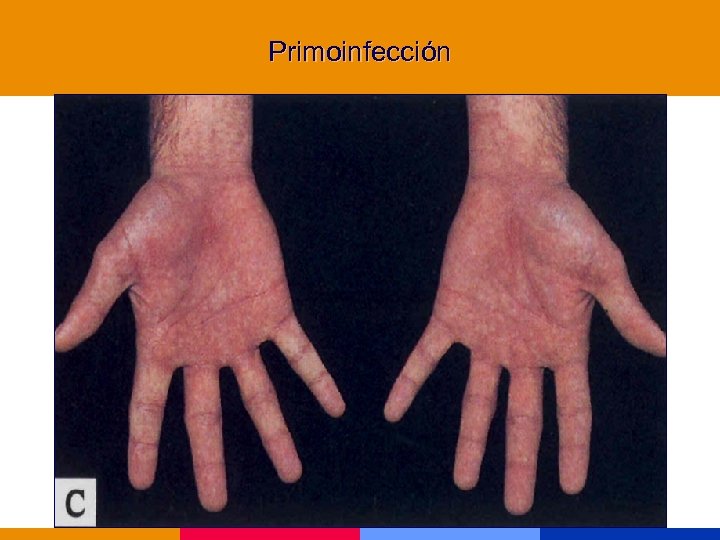

Primoinfección

Primoinfección

Primoinfección

Primoinfección

Primoinfección

Primoinfección

Primoinfección

Primoinfección